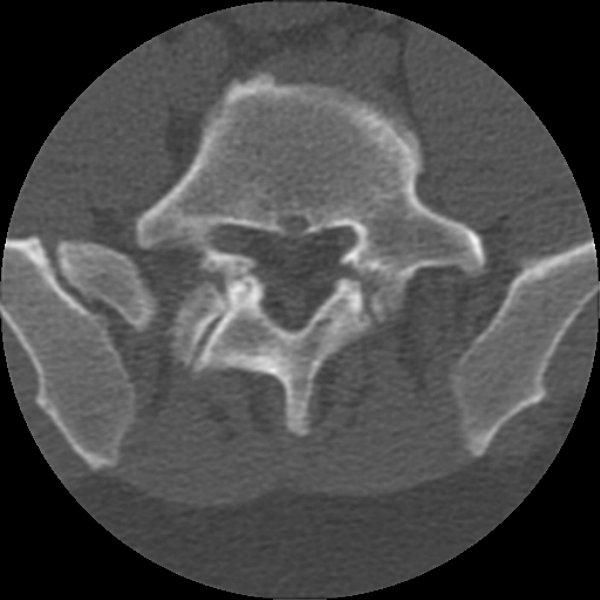

Return to Spondylolysis